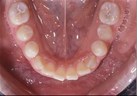

front view left buccal maxillary mandibular

Right Buccal View Frontal View Left Buccal View Maxillary View Mandibular View

Dental Casts

right buccal frontal left buccal upper mandibular